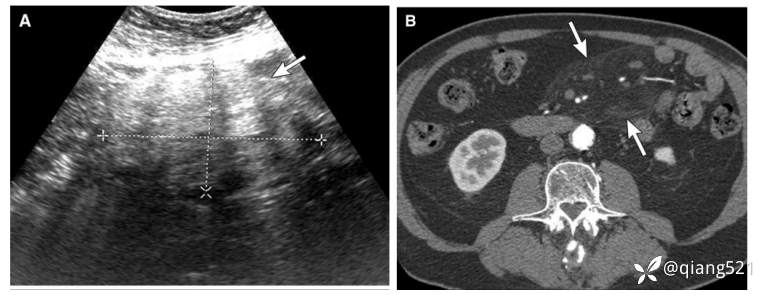

65岁男性,肠系膜脂膜炎。中腹部B超显示边界不清(箭头),轴位增强CT显示模糊的肠系膜脂肪伴小结节。